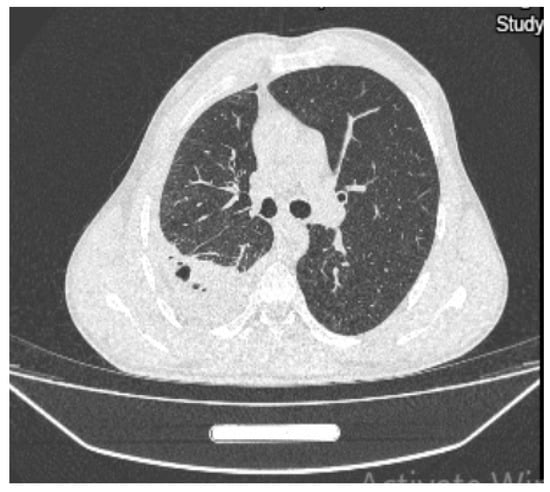

On the twentieth day, the chest X-ray showed multiple hydro-aerial levels up to 85/90 mm on the right lung (Figure 3). A chest computed tomography (CT) revealed free air and fluid levels within the pleural space with collapsed lung parenchyma (hydropneumothorax) and mediastinal lymphadenopaty (Figure 4).

Figure 4. Chest computed tomography showing hydropneumothorax.